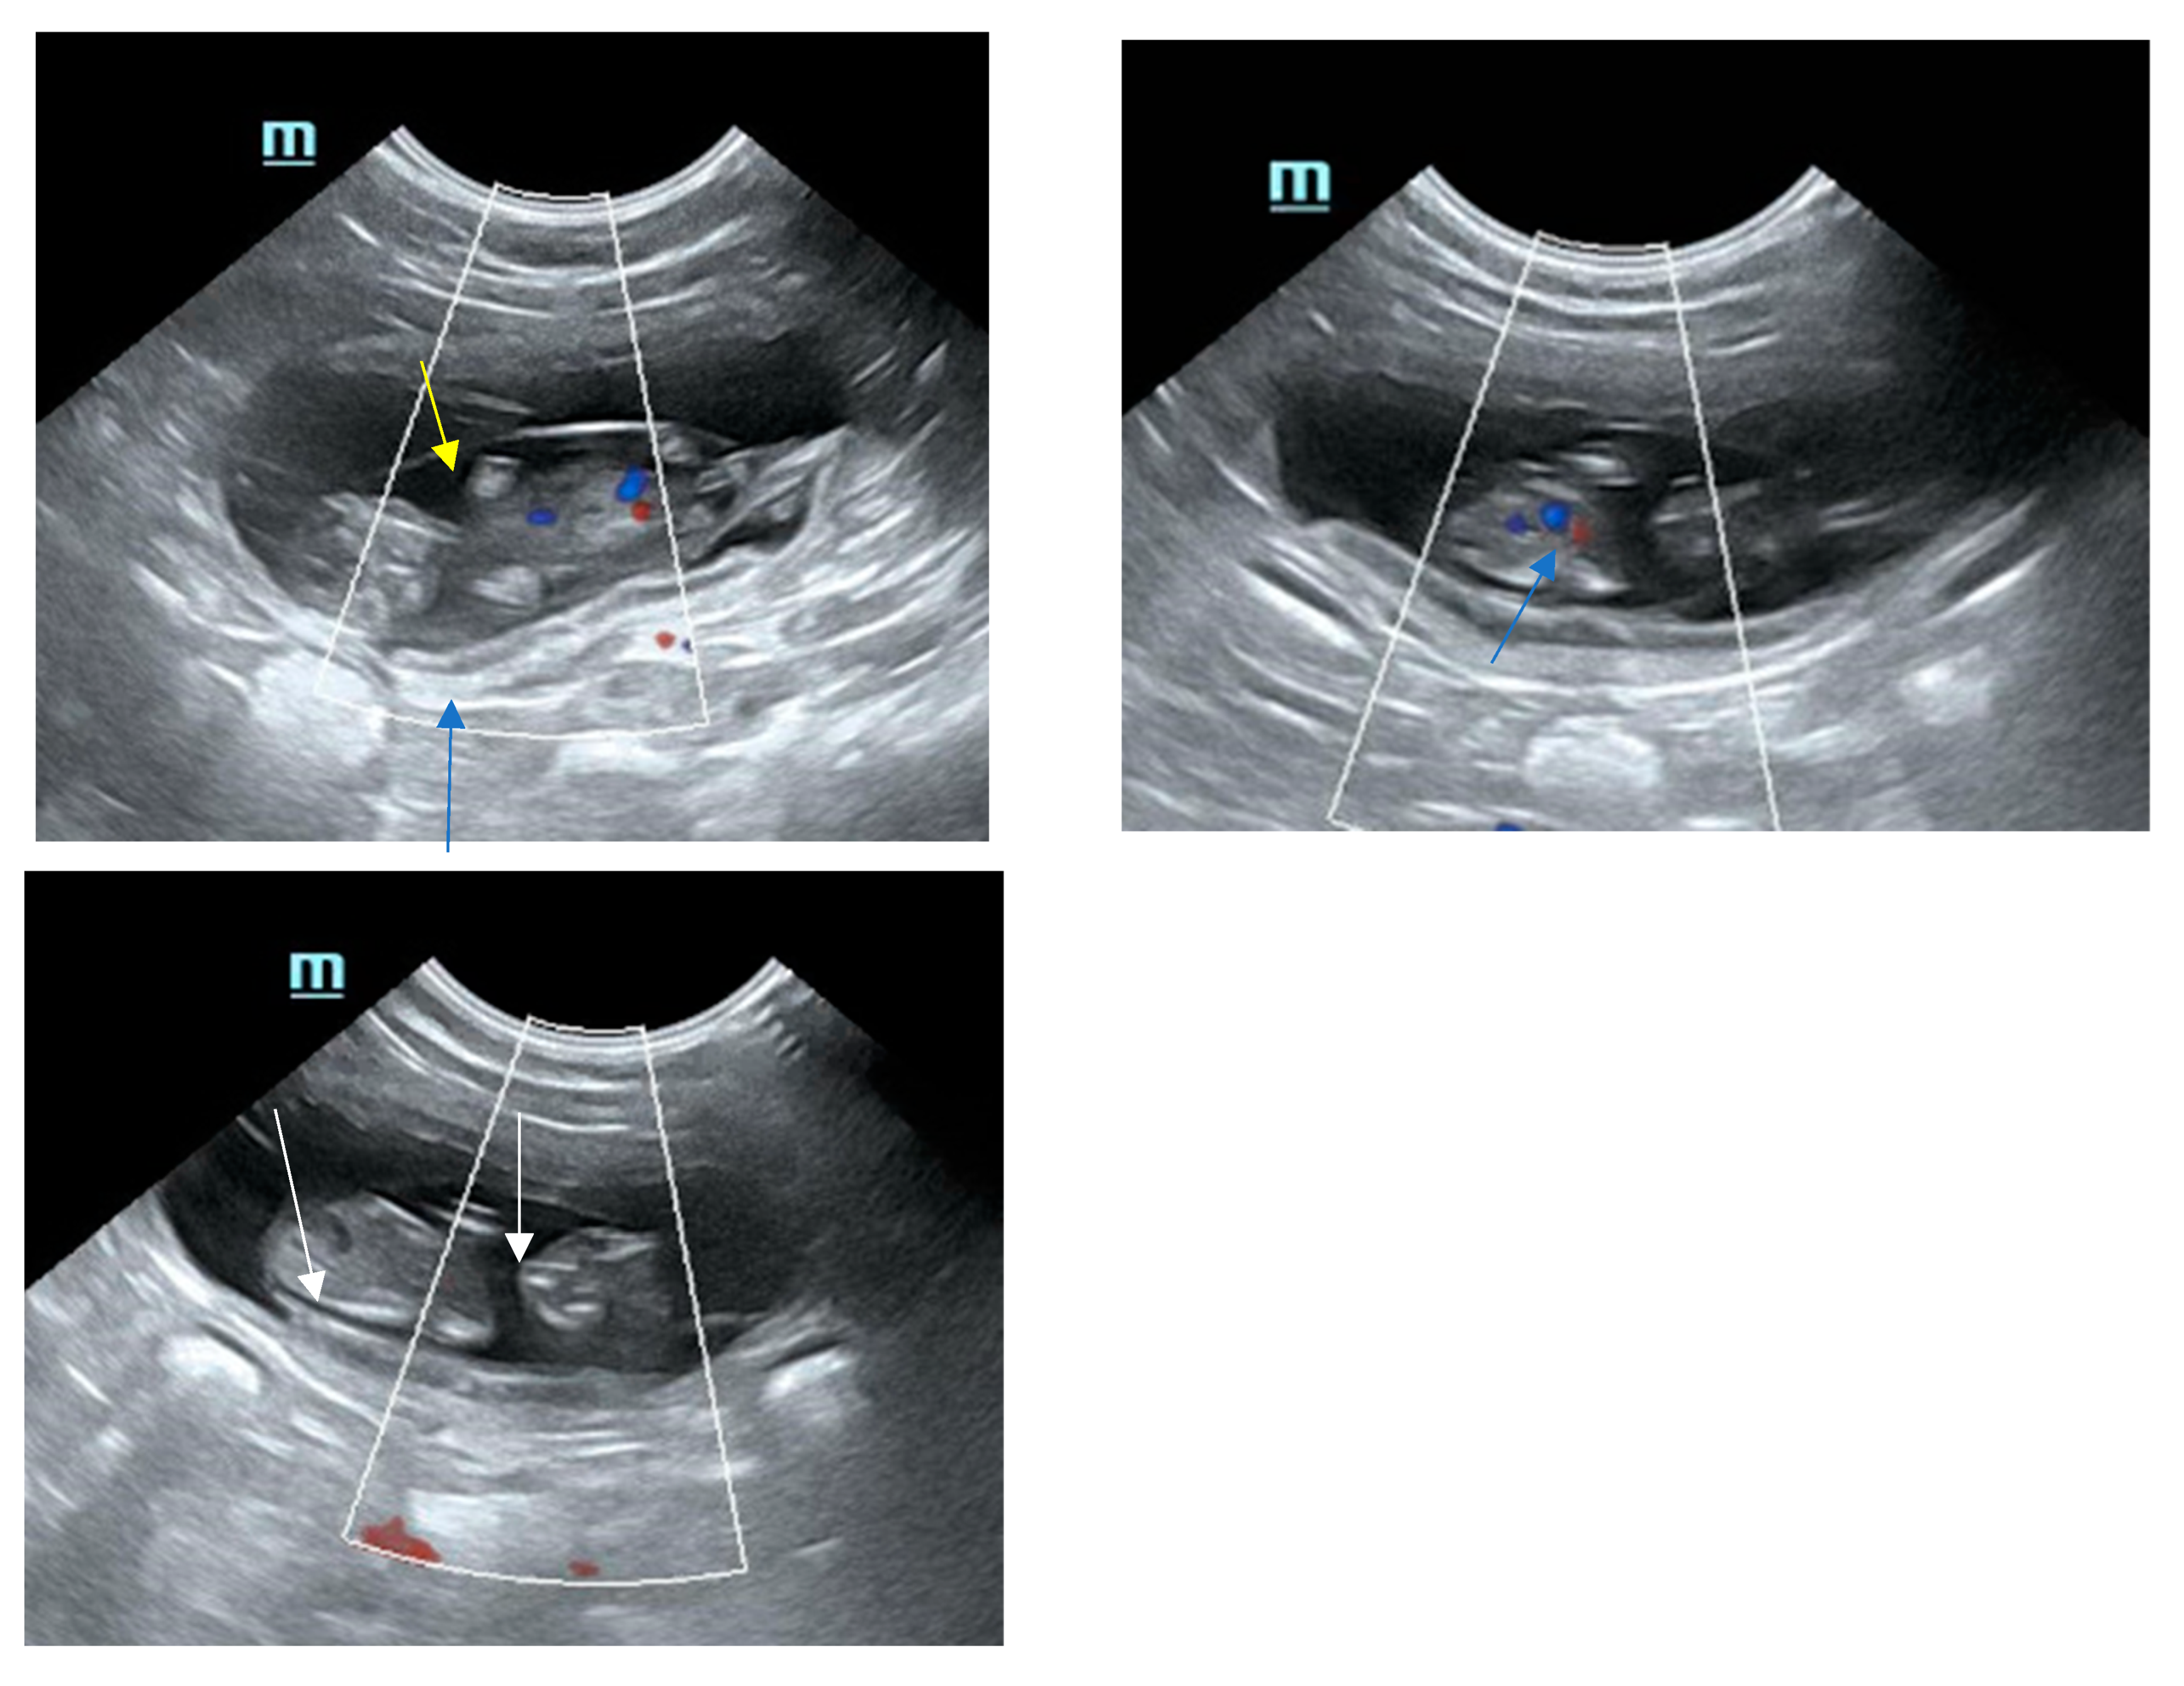

8. Sonographical Monitoring of the Developing Pregnancy

- Zambelli, D.; Castagnetti, C.; Belluzzi, S.; Bassi, S. Correlation between the age of the conceptus and various ultrasonographic measurements during the first 30 days of pregnancy in domestic cats (Felis catus). Theriogenology 2002, 57, 1981–1987. [Google Scholar] [CrossRef]

- Zambelli, D.; Prati, F. Ultrasonography for pregnancy diagnosis and evaluation in queens. Theriogenology 2006, 66, 135–144. [Google Scholar] [CrossRef] [PubMed]

- García Mitacek, M.C.; Stornelli, M.C.; Praderio, R.G.; de La Sota, R.L.; Stornelli, M.A. Ultrasonographic and progesterone changes during Days 21 to 63 of pregnancy in queens. Theriogenology 2015, 84, 1131–1141. [Google Scholar] [CrossRef]

- Lopate, C. Gestational Aging and Determination of Parturition Date in the Bitch and Queen Using Ultrasonography and Radiography. Vet. Clin. N. Am. Small Anim. Pract. 2018, 48, 617–638. [Google Scholar] [CrossRef]

- Górka, A.; Ochota, M.; Niżański, W. Ultrasound biometry for estimating delivery dates in small and medium breed cats. Theriogenology 2025, 232, 56–69. [Google Scholar] [CrossRef]

- Gatel, L.; Rault, D.N.; Chalvet-Monfray, K.; de Rooster, H.; Levy, X.; Chiers, K.; Saunders, J.H. Ultrasonography of the normal reproductive tract of the female domestic cat. Theriogenology 2020, 142, 328–337. [Google Scholar] [CrossRef]

- Zambelli, D.; Caneppele, B.; Bassi, S.; Paladini, C. Ultrasound aspects of fetal and extrafetal structures in pregnant cats. J. Feline Med. Surg. 2002, 4, 95–106. [Google Scholar] [CrossRef]